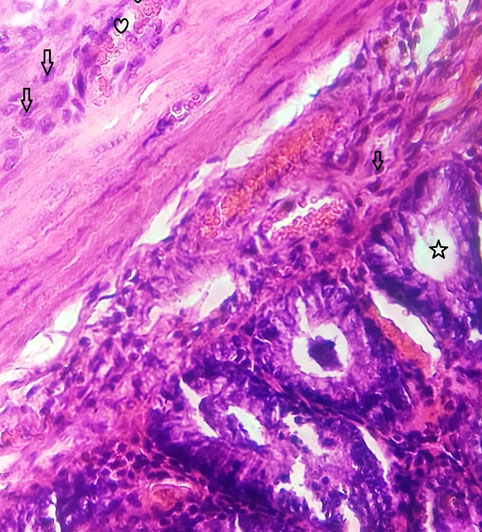

The rat liver tissue with the disturbed lobular arrangement is observed. Early necrotic and degenerative alterations extending lobules are visible. There are steatotic alterations and ballooning degenerations in hepatocytes. Some amount of fibrosis seen in portal tracts. Toxic injury with fibrotic alterations and mild necrosis is observed in the liver (Fig. 3).

Fig. (3). Toxic injury with fibrotic alterations and mild necrosis is observed in the liver. |